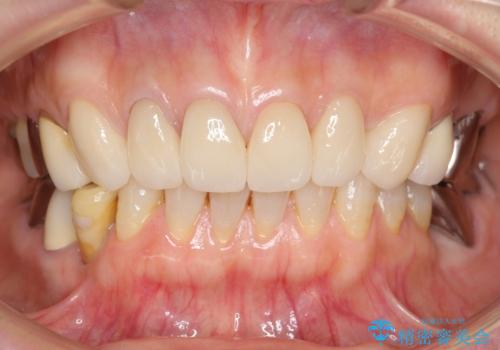

治療した上の前歯6本は全く問題なく、「獅子舞みたいだった前歯を綺麗にして下さってありがとうございました!」と再度お礼を言って下さいました。

4年半前のクラウン装着時と変わらず、まるで天然歯のように自然に見えました。

患者様の良好なセルフケアと精密な適合の良いクラウンにより、歯肉の腫脹や退縮も認められませんでした。

4年半前に行った治療に大変ご満足頂き、他の部位の治療のため再来院して下さいました。